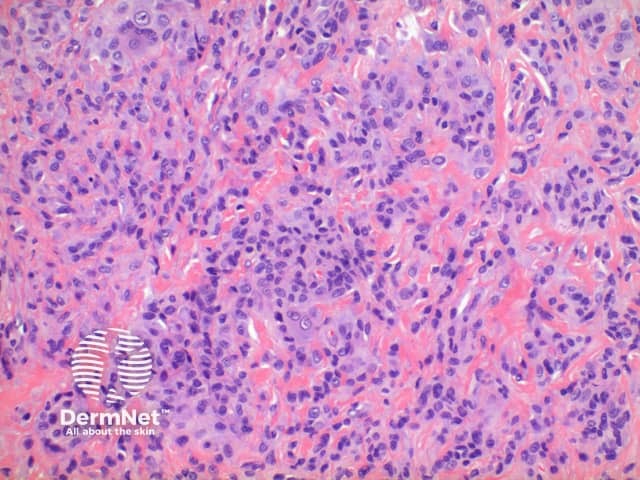

Scanning power view of giant cell tumour of tendon sheath identifies a well circumscribed tumour nodule arising in the deep dermis or subcutis (Figures 1-3). The tumour nodule is comprised of a population of oval cells set in a minor condensed eosinophilic fibrous stroma (Figures 4 and 5). Scattered multinucleated giant cells are present (Figure 6). In most cases small clusters of lipid laden cells can be seen (Figures 7 and 8) .